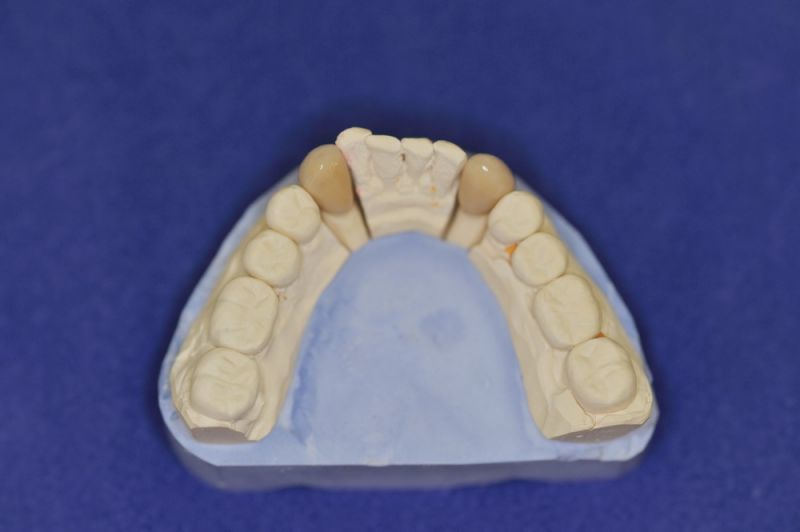

Der Patient erhält die beiden letzten Kronen zur Einstellung der dynamischen Okklusion.

In diesem Fall möglich über die Herstellung von zwei Eckzahnkronen